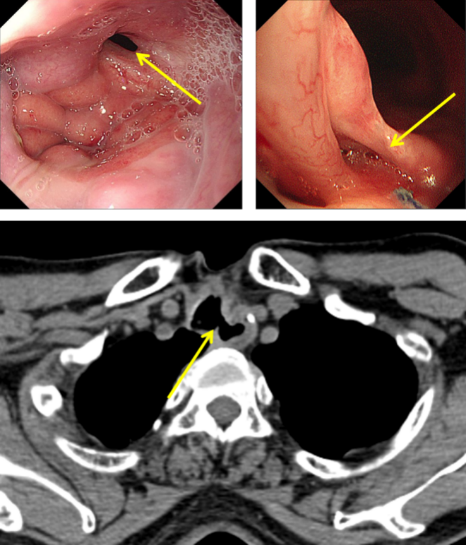

圖1:氣管食管瘺口

經(jīng)推薦,老秦慕名來到我院胸外科胡楊副主任醫(yī)師處就診。經(jīng)檢查發(fā)現(xiàn),老秦的病情與其他氣管食管瘺患者相比,更為復雜和嚴重:一是瘺口所處位置較為“刁鉆”。患者氣管食管間瘺口位于頸胸交界部位,無論是從頸部或是胸部入路均難以充分暴露瘺口;二是瘺口情況較為糟糕。該患者于外院多次行瘺口修補手術,瘺口附近勢必粘連嚴重、組織結(jié)構(gòu)難以辨認,損傷喉返神經(jīng)、頸胸部血管等重要結(jié)構(gòu)的風險高;組織血供破壞嚴重,術后缺血壞死風險高;三是患者營養(yǎng)嚴重不足。該患者由于“氣管食管瘺”已兩年未經(jīng)口進食,身體非常虛弱。